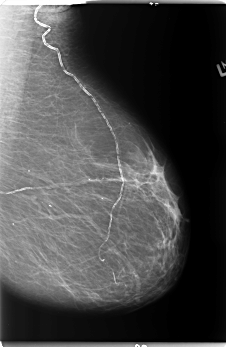

B_3141_1.RIGHT_CC

LEFT_CC LINES 5912 PIXELS_PER_LINE 3584 BITS_PER_PIXEL 12 RESOLUTION 50 NON_OVERLAY

RIGHT_CC LINES 5880 PIXELS_PER_LINE 3472 BITS_PER_PIXEL 12 RESOLUTION 50 OVERLAY